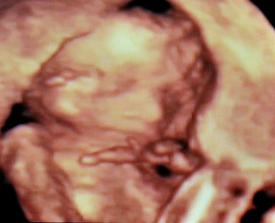

✿♥♥♥♥Bude to dievčatko!!!!! ♥♥♥♥✿

Bude to Stella 🙂

krasne 3D sono 🙂